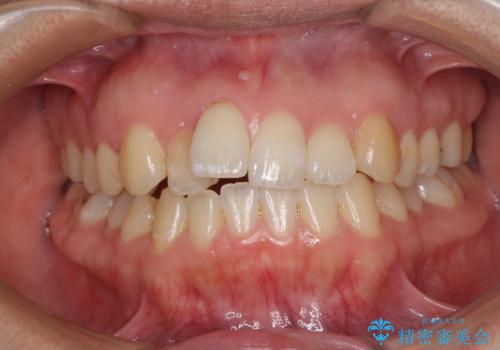

- 上下のデコボコを改善したいとのことで来院された患者様です。

近々妊娠する予定であり、極力短期間で治療したいとのことで、ワイヤー装置による非抜歯矯正治療を行うこととしました。